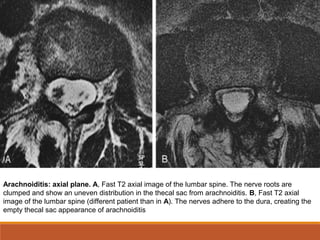

Arachnoiditis: axial plane. A, Fast T2 axial image of the lumbar spine. The nerve roots are

clumped and show an uneven distribution in the thecal sac from arachnoiditis. B, Fast T2 axial

image of the lumbar spine (different patient than in A). The nerves adhere to the dura, creating the

empty thecal sac appearance of arachnoiditis

Aracnoidite:

◦Na RM, os achados são mais bem visualizados em T2:

◦ As raízes nervosas podem estar unidas ao invés de igualmente distribuídas

através do saco tecal.

◦ Nervos podem ficar aderidos à dura-máter de modo que pareça que o saco

tecal esteja vazio, sem raízes nervosas presentes.

◦ Nas imagens sagitais, os nervos da cauda eqüina podem ter uma aparência

irregular, angulada ou ondulada, em lugar da curva descendente suave

normal.